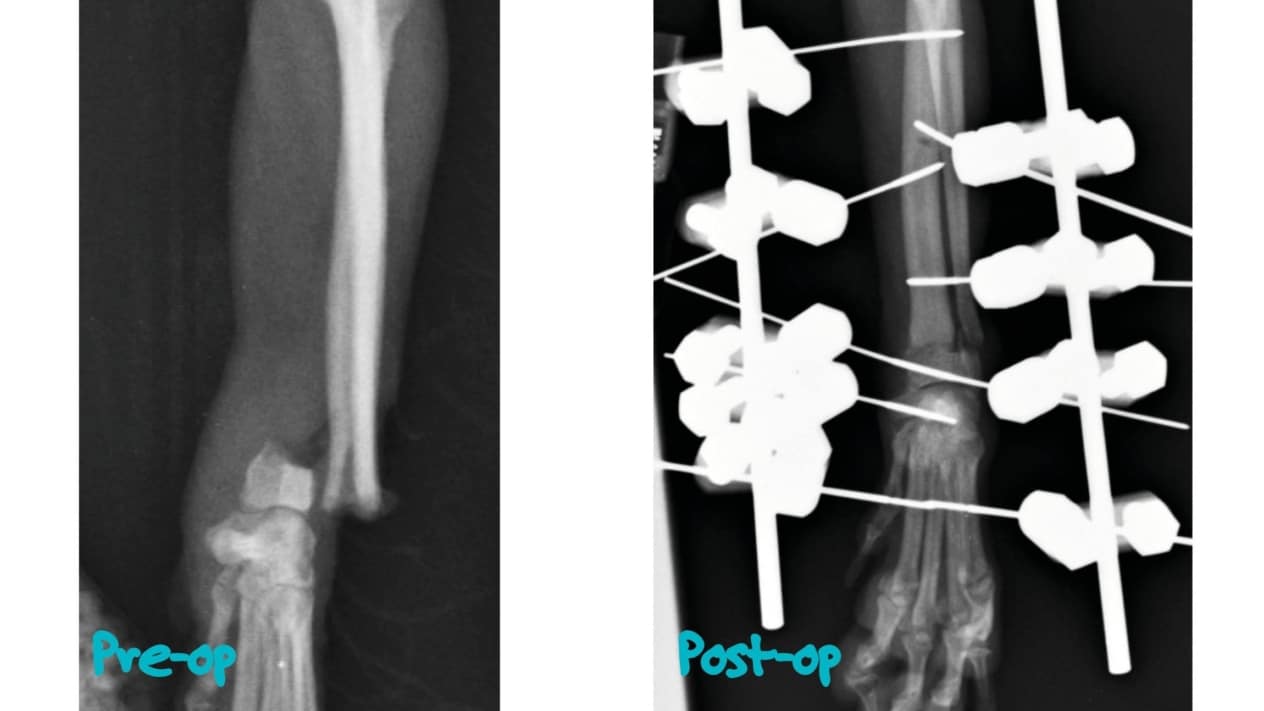

At the veterinary clinic, the doctor will diagnose the injury using digital x-rays and ultrasound machines. The veterinarian will determine the complexity of the injury and select the best individualized treatment method for your Ponytail, so that your pet can return to normal life as soon as possible. Diagnosis is necessary to determine the most effective method of treatment for the fracture: whether fixing the pet’s limb, resting it, restricting physical activity, taking medication, or possibly surgery, physical therapy and a special period of rehabilitation will be sufficient.

Paw fracture can be: complete and incomplete, closed or open, single or multiple. To treat complex fractures, modern veterinary medicine uses the method of osteosynthesis – a surgical operation – fixation of damaged bones with special constructions: plates, spokes, pins, screws. Immediately after such an operation, the animal begins to stand on the paw. Conservative method – plastering – can be applied only when it is impossible to perform surgery. In 90% of cases, a fracture of the paw in dogs and cats heals very quickly if the first aid is given in time and the method of treatment is chosen correctly.